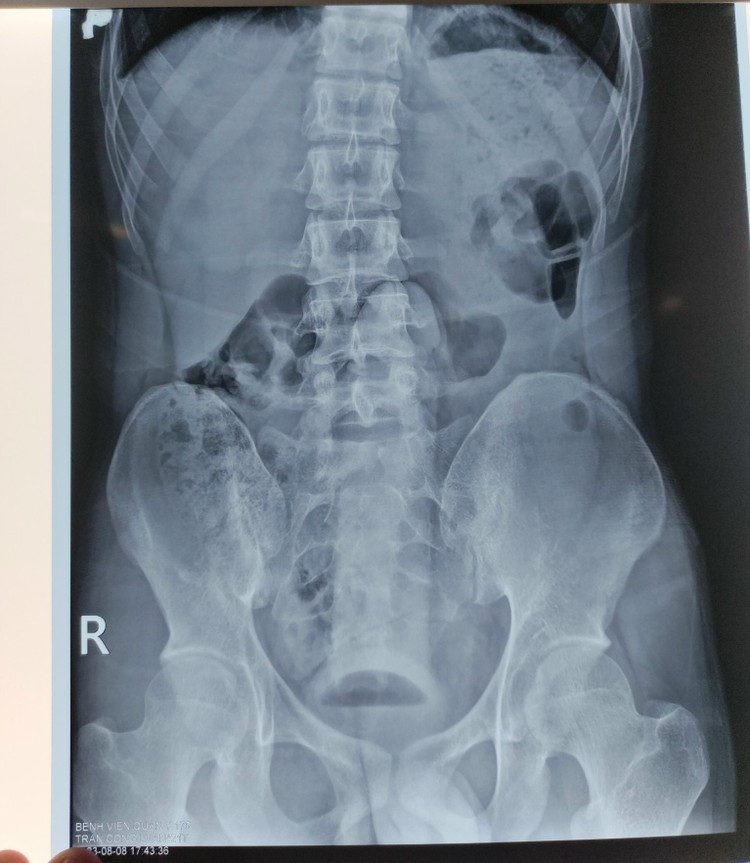

Qua phim X-Quang, các bác sĩ phát hiện dị vật đã chui sâu vào trong trực tràng của nam bệnh nhân |

Bệnh nhân được đưa đến khoa Cấp cứu, Bệnh viện Quân y 175, sau khi thăm khám và chụp Xquang, các bác sĩ đã phát hiện trực tràng có dị vật hình dạng giống “dương vật” nằm sâu trong trực tràng nên bệnh nhân được chuyển lên khoa Phẫu thuật – gây mê hồi sức tiến hành lấy dị vật.

Qua phim X-Quang, các bác sĩ phát hiện dị vật đã chui sâu vào trong trực tràng của nam bệnh nhân